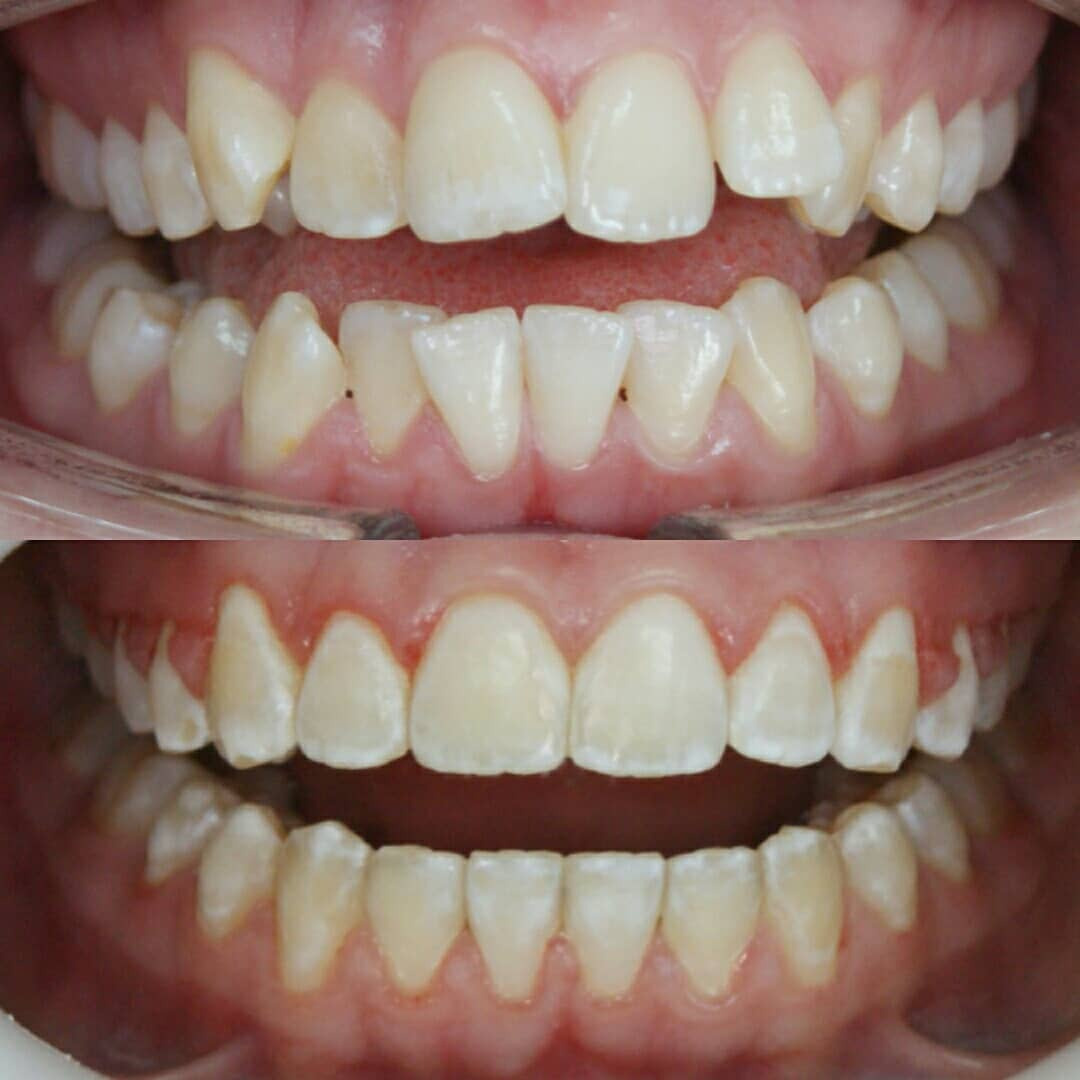

✔Глубокий прикус, дистальный прикус с пространством (щелью) между верхними и нижними резцами, скученное положение зубов, заблокированное нёбное положение верхнего левого зуба ✔Лечение на металлической самолигирующей системе Damon

✔Пациент, 12,5 лет на момент старта ✔Общий срок лечения 18 месяцев ✔Брекеты Damon Q ✔Дистальный, перекрестный, глубокий прикус, смещение нижней челюсти, несоответствие средних линий и сужение зубных рядов, скученность зубов, недостаток места для верхних клыков